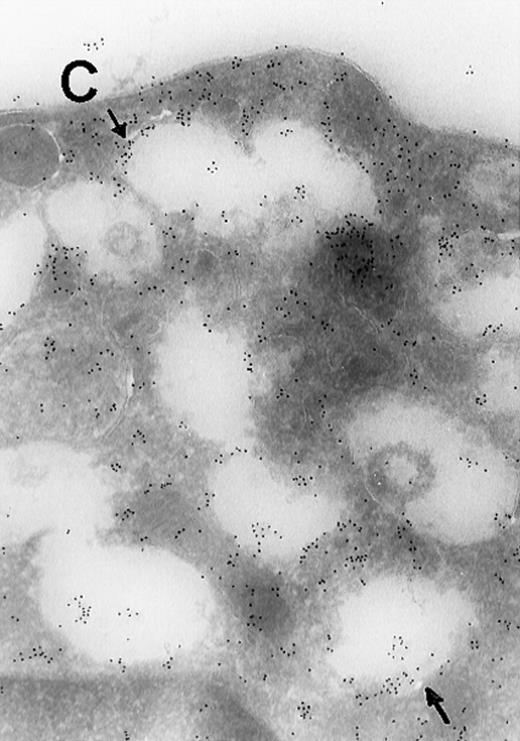

In view of these reports, we determined the cellular localization of MAP kinase in megakaryocytes, with a particular attention to the platelet-yielding demarcation membranes.7As a control, we determined the localization of another TPO-upregulated serine/threonine kinase, Mst1.8 Our current Electron Microscopic (EM) studies, performed as we described before,9 reveal that a significant fraction of MAP kinase, but none of Mst1, localizes to the demarcation membranes. In resting platelets, MAP kinase is found in a cluster pattern associated with the plasma membrane (which is believed to originate from the megakaryocytic demarcation membranes),7 as well as over electron-dense cytoplasmic domains (Figure). In view of our finding that MAP kinase is localized to the demarcation membranes in megakaryocytes, it is of interest to note that this kinase was also shown to be localized in Golgi membranes and involved in their fragmentation during mitosis in a microtubule-dependent manner.10 Platelet fragmentation likely involves the cytoskeleton, and perhaps MAP kinases are also involved in this process.

(A) Ultrathin frozen sections of rat platelets immunolabeled with antibodies to ERK (magnification ×45 000). (B) Well-developed demarcation membranes in a rat (Wistar), TPO-treated megakaryocyte7 9 immunostained with an antibody to Mst1 (magnification ×48 000), or (C) with an antibody to ERK, which recognizes ERK1 and ERK2 (magnification ×65 400). The arrows point to the demarcation membranes. The Mst1 antiserum (gift of Dr Jonathan Chernoff, Fox Chase Cancer Center, Philadelphia, PA) and anti-ERK2 (K-23) (Santa Cruz Biotechnology, Santa Cruz, CA) or TR2, anti-ERK (gift of Michael Weber, University of Virginia Medical School) were diluted 1:10.